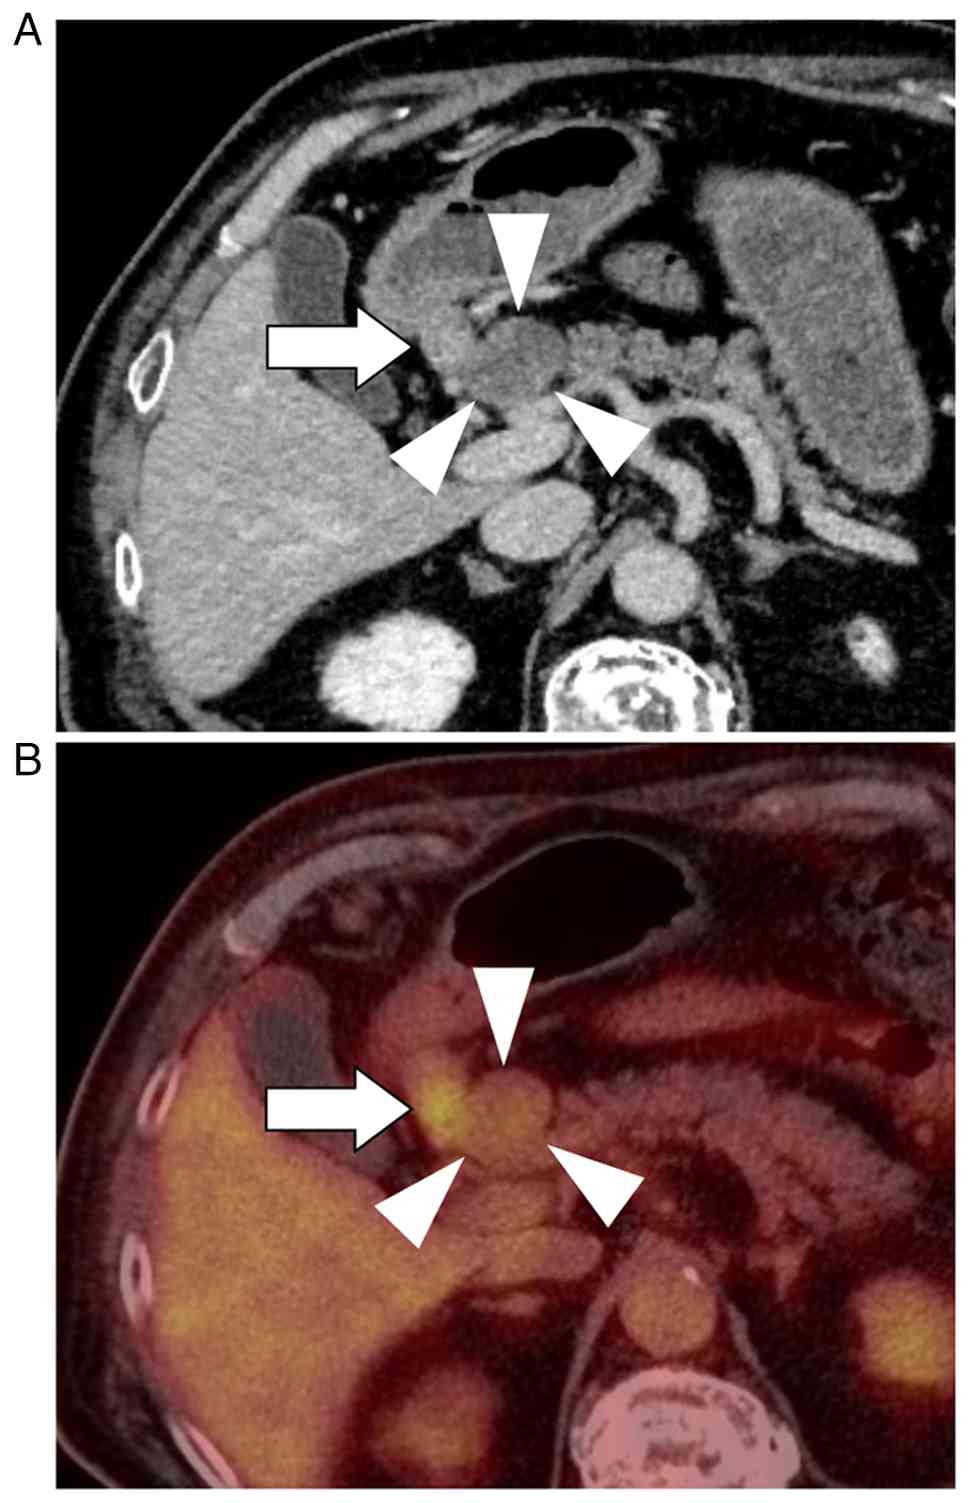

Subsequent imaging demonstrated a 30-mm protruding mass in the pancreatic head, characterized by hypodensity in the arterial phase and gradual enhancement in the portal and venous phases, along with an enlarged lymph node in the infrapyloric region (Fig. 1A). Positron emission tomography-computed tomography demonstrated increased FDG uptake in both the pancreatic head lesion (SUVmax, 2.74) and the infrapyloric lymph node (station No. 6; SUVmax, 6.28), whereas no abnormal uptake was observed in the gastric wall (Fig. 1B). Esophagogastroduodenoscopy was performed with careful inspection of the entire stomach, including the antrum and pyloric region. No endoscopically identifiable lesion suggestive of primary gastric cancer was detected (Fig. S1). Endoscopic ultrasound (EUS)-guided biopsy of the enlarged infrapyloric lymph node demonstrated adenocarcinoma; however, the primary site of origin could not be determined. EUS-guided sampling of the pancreatic head lesion itself was not performed, as a safe and reliable puncture route could not be secured due to intervening vascular structures.

Radiologic imaging of a tumor in the

pancreatic head. (A) Abdominal contrast-enhanced computed

tomography shows 30-mm protruding mass in the pancreatic head with

hypodensity (arrowheads), along with enhanced lymph nodes in the

infrapyloric region (arrow). (B) Positron emission

tomography-computed tomography reveals an abnormal uptake in both

the pancreatic head lesion (arrowheads) and lymph nodes in the

infrapyloric region (arrow).

Figure 1.

Radiologic imaging of a tumor in the pancreatic head. (A) Abdominal contrast-enhanced computed tomography shows 30-mm protruding mass in the pancreatic head with hypodensity (arrowheads), along with enhanced lymph nodes in the infrapyloric region (arrow). (B) Positron emission tomography-computed tomography reveals an abnormal uptake in both the pancreatic head lesion (arrowheads) and lymph nodes in the infrapyloric region (arrow).